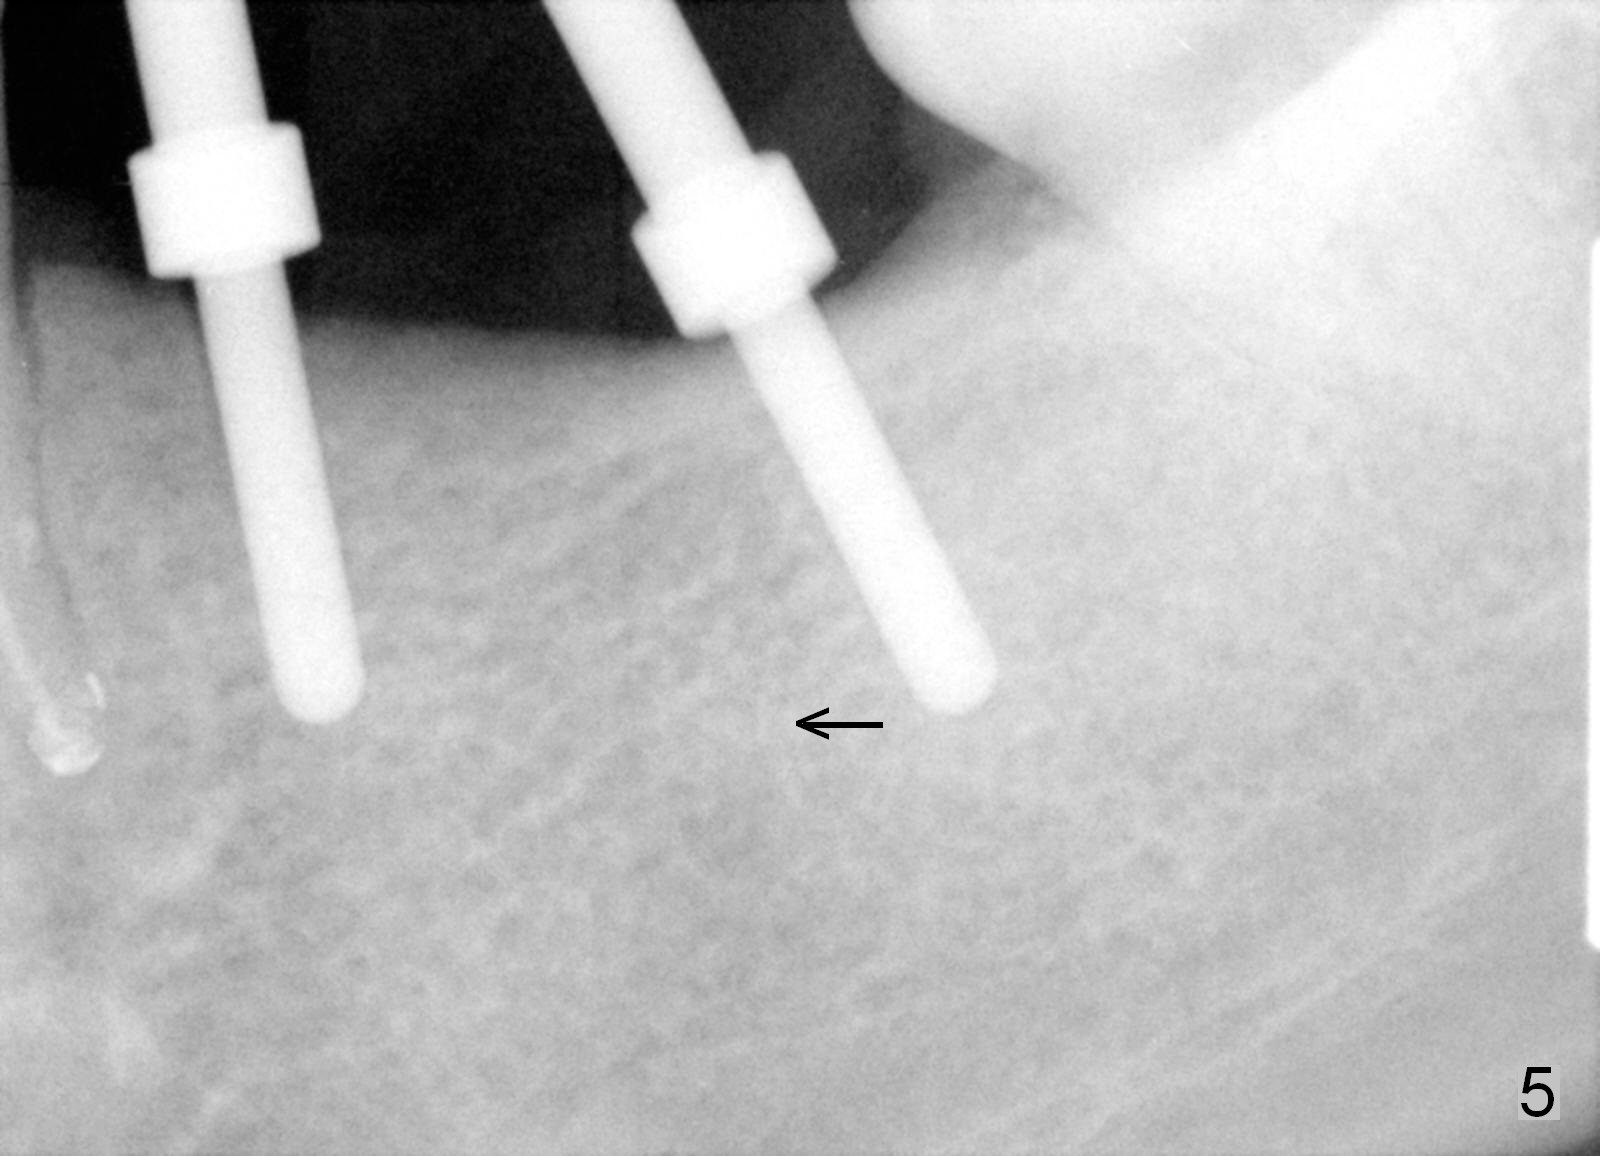

One year 2 months post root canal therapy at #20 (Fig.4), osteotomies are initiated at #18 and 19.  The trajectory at #19 is subsequently corrected (Fig.5); that of #18 should be also corrected (arrow).  The fact of the narrow ridge (Fig.6) is also ignored intraop.  Without further adjustment, the osteotomies are enlarged (Fig.7) and the implants are placed (Fig.8: 4.5x14, 5x14 mm).  As expected, the buccal coronal implant surface is exposed.  The buccal plate is decorticated with placement of autogenous bone graft.  Periodontal dressing is applied.  Postop, the wound is infected with wound gapping.  With irrigation, the wound finally heals.